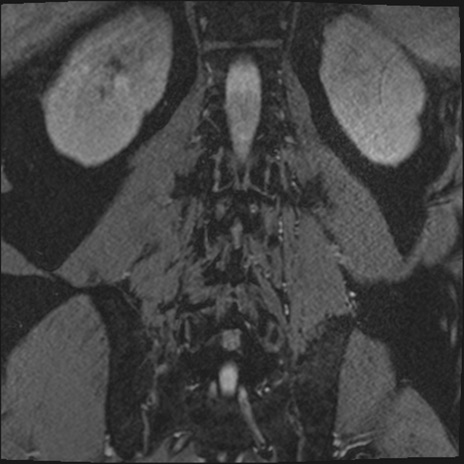

【整形】TIPS症例2 腰椎MRI 3D(冠状断像)

【症例】70歳代男性

【主訴】左下肢痛

【現病歴】2週間前くらいから腰痛、左下肢痛あり。左臀部から大腿、下腿外側のしびれが常時ある。歩行とともに同部位の痛みあり。

【身体所見】Lasegue70-/60+、Bragard-/±、PTR ±/±、ATR -/-、IP 5/5、TA 5/4、TS 5/5、EHL 右第1足趾なし/3、FHL 5/5、hypersthesia(-)、足背動脈触知良好

異常所見と診断は?